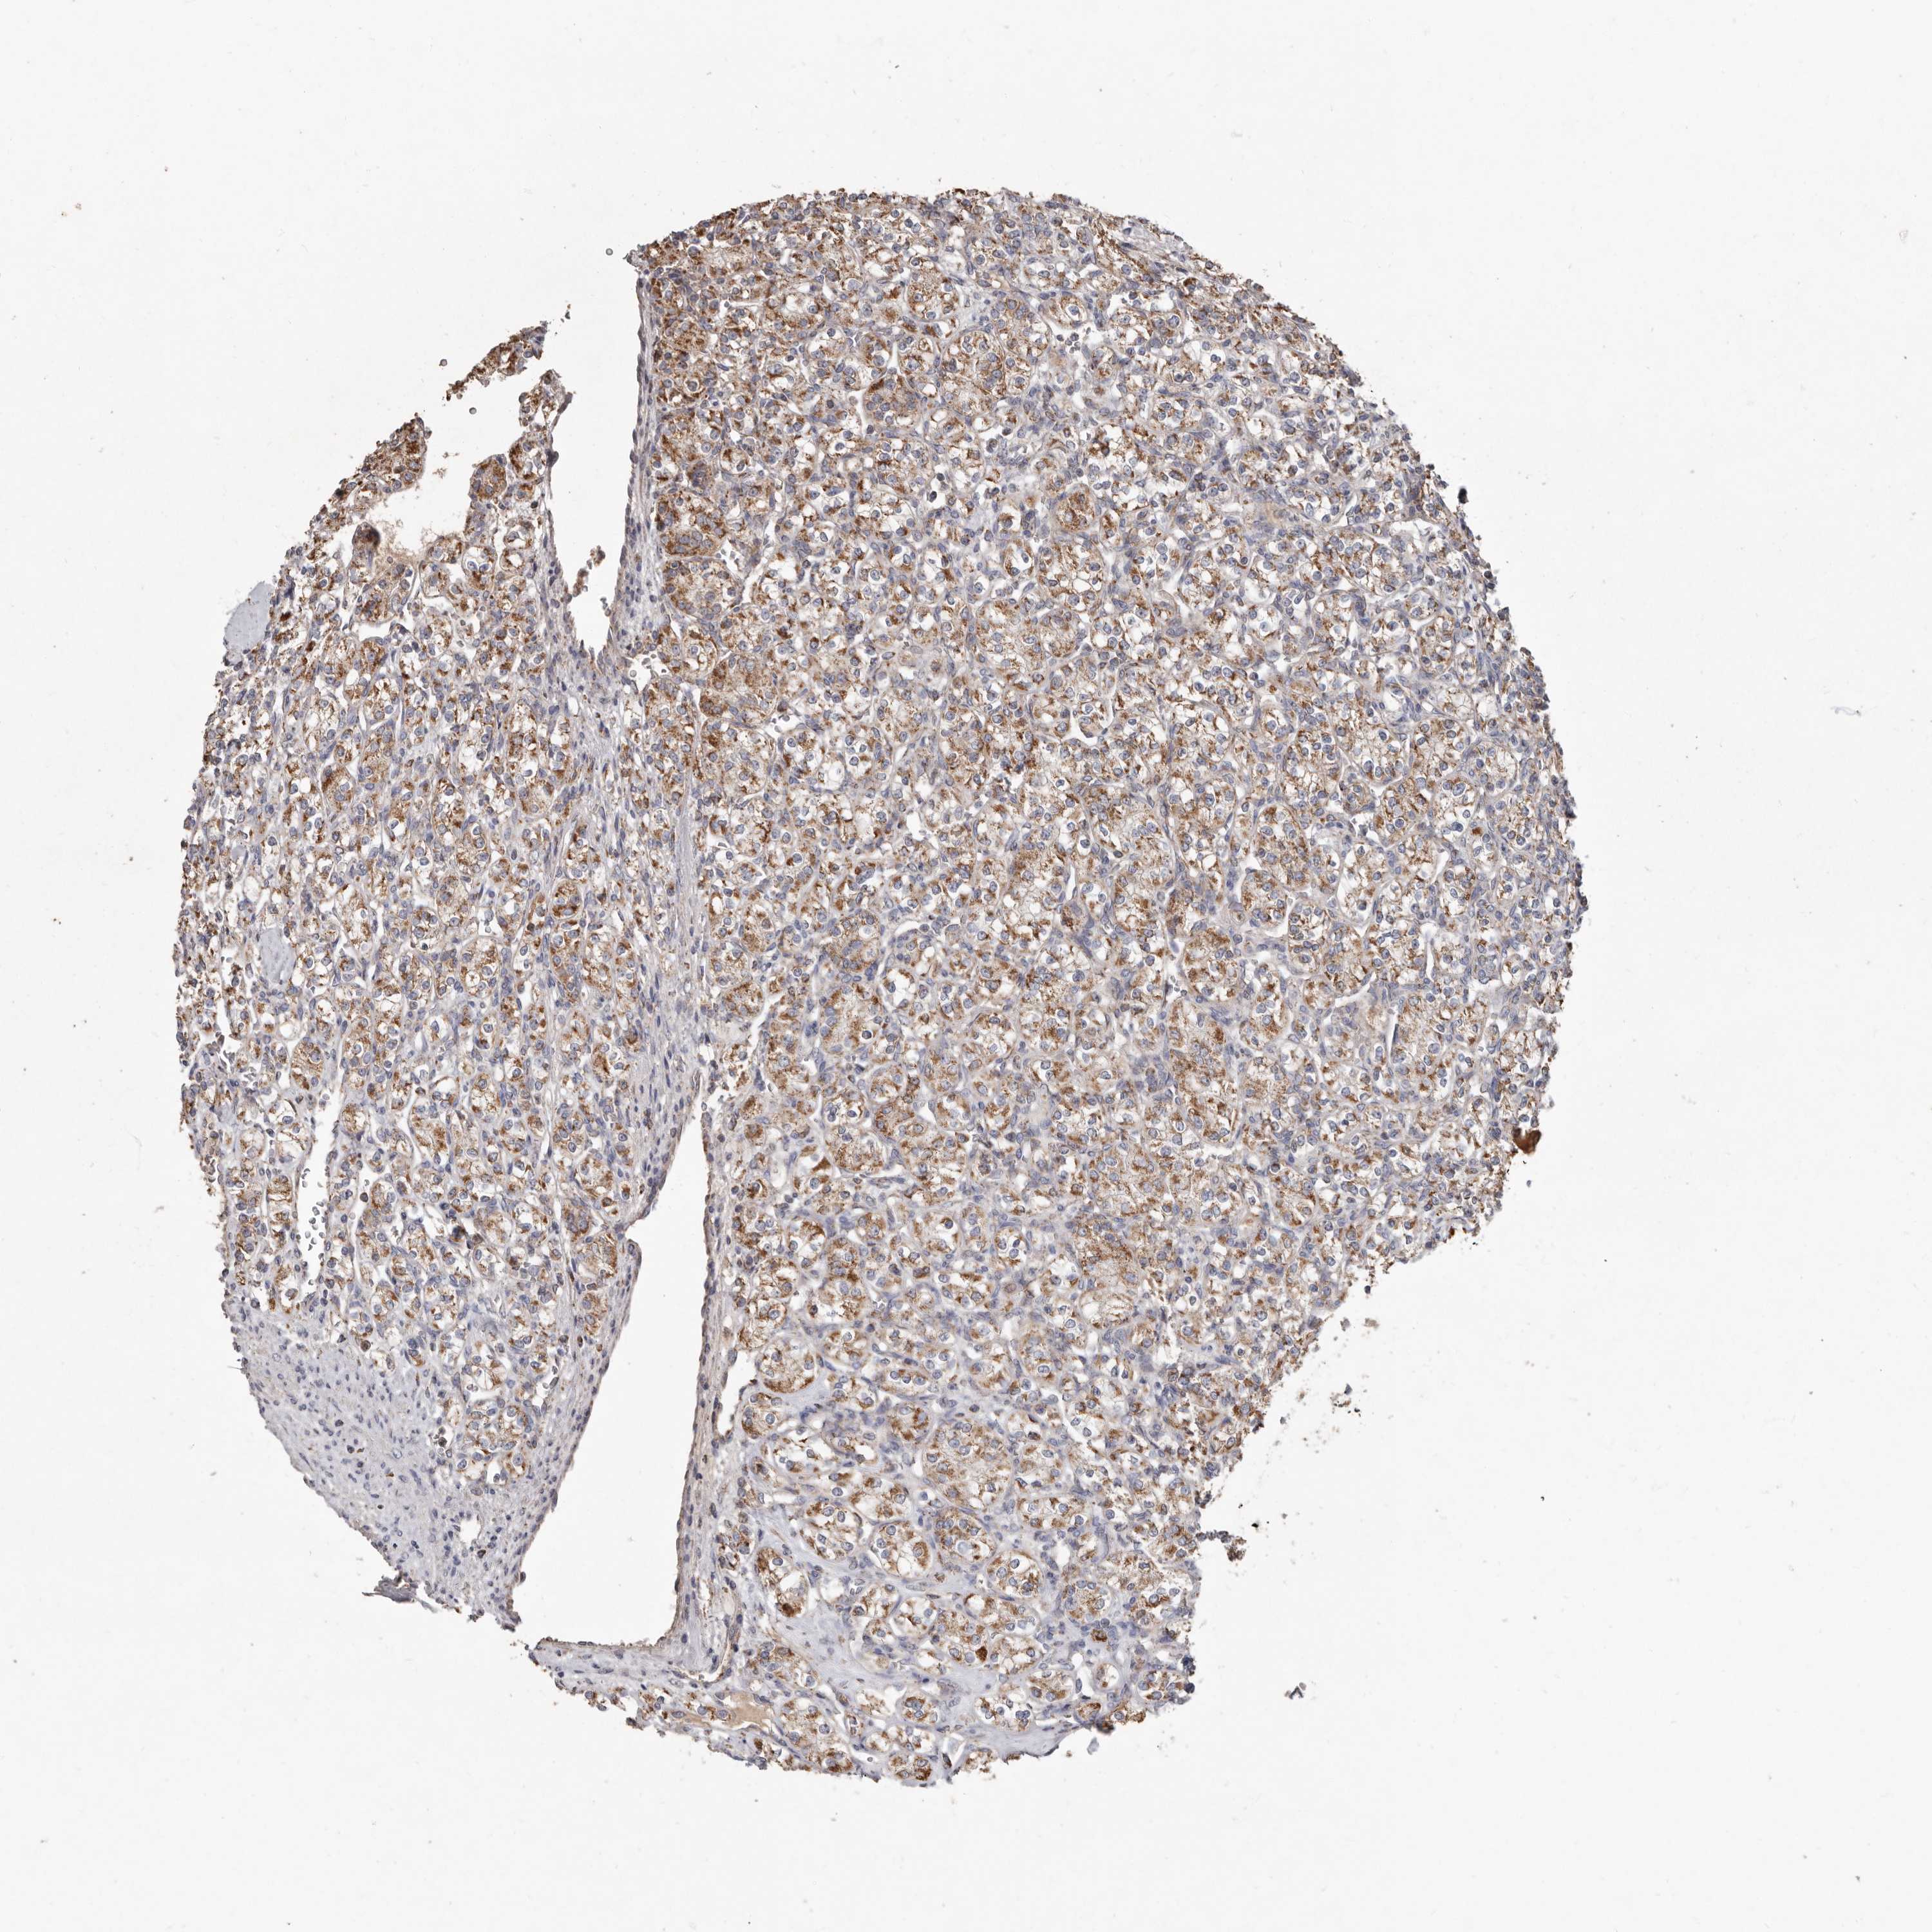

KIDNEY RENAL CLEAR CELL CARCINOMA (VALIDATION) - Interactive survival scatter ploti

The Survival Scatter plot shows the clinical status (i.e. dead or alive) for all individuals in the patient cohort, based on the same data that underlies the corresponding Kaplan-Meier plots. Patients that are alive at last time for follow-up are shown in blue and patients who have died during the study are shown in red.

The x-axis shows the expression levels (FPKM) of the investigated gene in the tumor tissue at the time of diagnosis. The y-axis shows the follow-up time after diagnosis (years). Both axes are complimented with kernel density curves demonstrating the data density over the axes. The top density plot shows the expression levels (FPKM) distribution among dead (red) and alive patients (blue). The right density plot shows the data density of the survived years of dead patients with high and low expression levels respectively, stratified using the cutoff indicated by the vertical dashed line through the Survival Scatter plot. This cutoff is automatically defined based on the FPKM cutoff that minimizes the p-score. The cutoff can be changed by dragging the vertical line or by entering a cutoff value in the square labeled "Current cut-off".

Under the Survival Scatter plot the p-score landscape (black curve; left axis) is shown together with dead median separation (red curve; right axis). Dead median separation is the difference in median mRNA expression between patients who have died with high and low expression, respectively. It is calculated as follows: median FPKM expression of dead patients with high expression - median FPKM expression of dead patients with low expression. This is intended to aid the user in visually exploring custom cutoffs and the associated p-scores and dead median separation.

Individual patient data is displayed and can be filtered by clicking on one or more of the category buttons on the top of the page. Categories describing expression level and patient information include: high, low, alive, dead, female, male and tumor stages. The scale of the x-axis can be toggled between linear and log-scale by clicking on the "x log" button. Mouse-over function shows TCGA ID, patient information and mRNA expression (FPKM) for each patient.

& Survival analysisi

Kaplan-Meier plots summarize results from analysis of correlation between mRNA expression level and patient survival. Patients were divided based on level of expression into one of the two groups "low" (under cut off) or "high" (over cut off). X-axis shows time for survival (years) and y-axis shows the probability of survival, where 1.0 corresponds to 100 percent.

KIF26B is not prognostic in Kidney Renal Clear Cell Carcinoma (validation)

TCGA RNA samplesi

RNA-seq data is reported as average FPKM (number Fragments Per Kilobase of exon per Million reads), generated by the The Cancer Genome Atlas (TCGA) .

Normal distribution across the dataset is visualized with box plots, shown as median and 25th and 75th percentiles. Points are displayed as outliers if they are above or below 1.5 times the interquartile range. FPKM values of the individual samples are presented next to the box plot.

Average pTPM 0.8

Number of samples 100